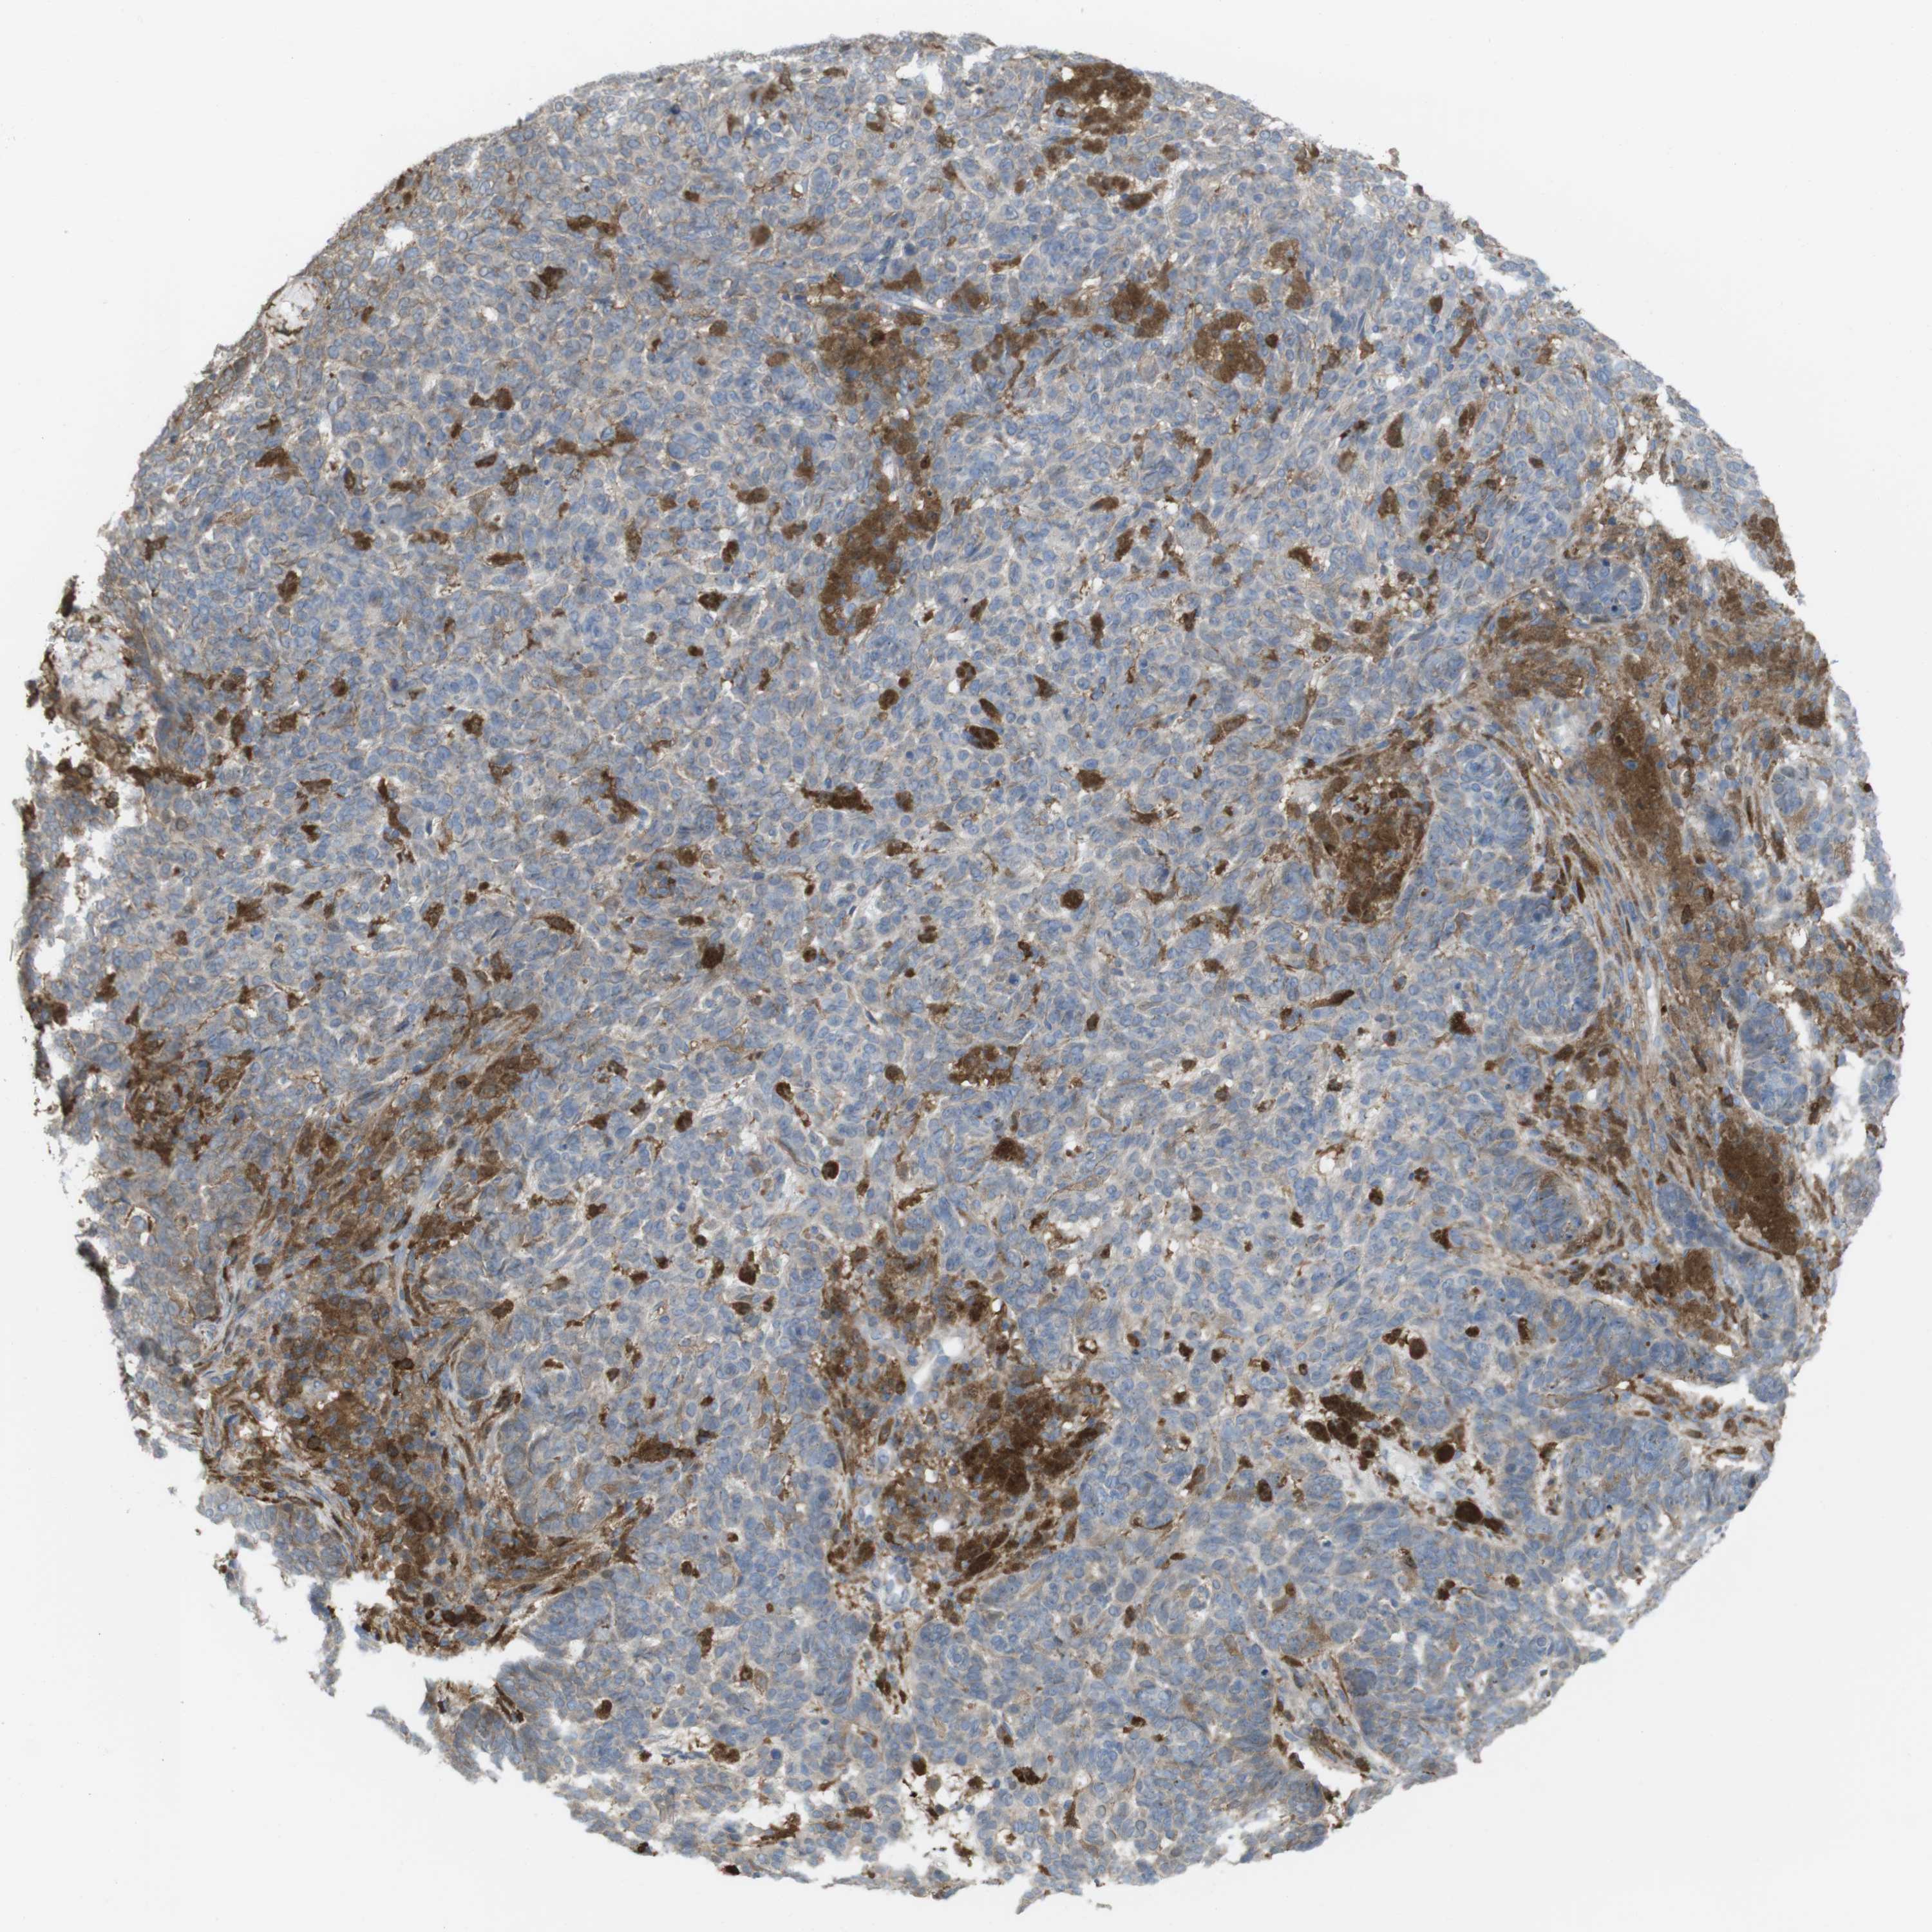

SKIN CANCER - Protein expressioni

A mouse-over function shows sample information and annotation data. Click on an image to view it in a full screen mode. Samples can be filtered based on level of antibody staining by selecting one or several of the following categories: high, medium, low and not detected. The assay and annotation is described here.

Each image is clickable and will lead to virtual microscopy that enables deeper exploration of all samples and also displays staining intensity scores, fraction scores and subcellular localization as well as patient and tissue information for each sample.

Antibody HPA001890

Staining

High

Medium

Low

Not detected

Intensity

Strong

Moderate

Weak

Negative

Quantity

>75%

75%-25%

<25%

None

Location

Nuclear

Cytoplasmic/membranous

Cytoplasmic/membranous,nuclear

Squamous cell carcinoma, NOS

Basal cell carcinoma

Squamous cell carcinoma in situ, NOS

Adnexal tumor, benign